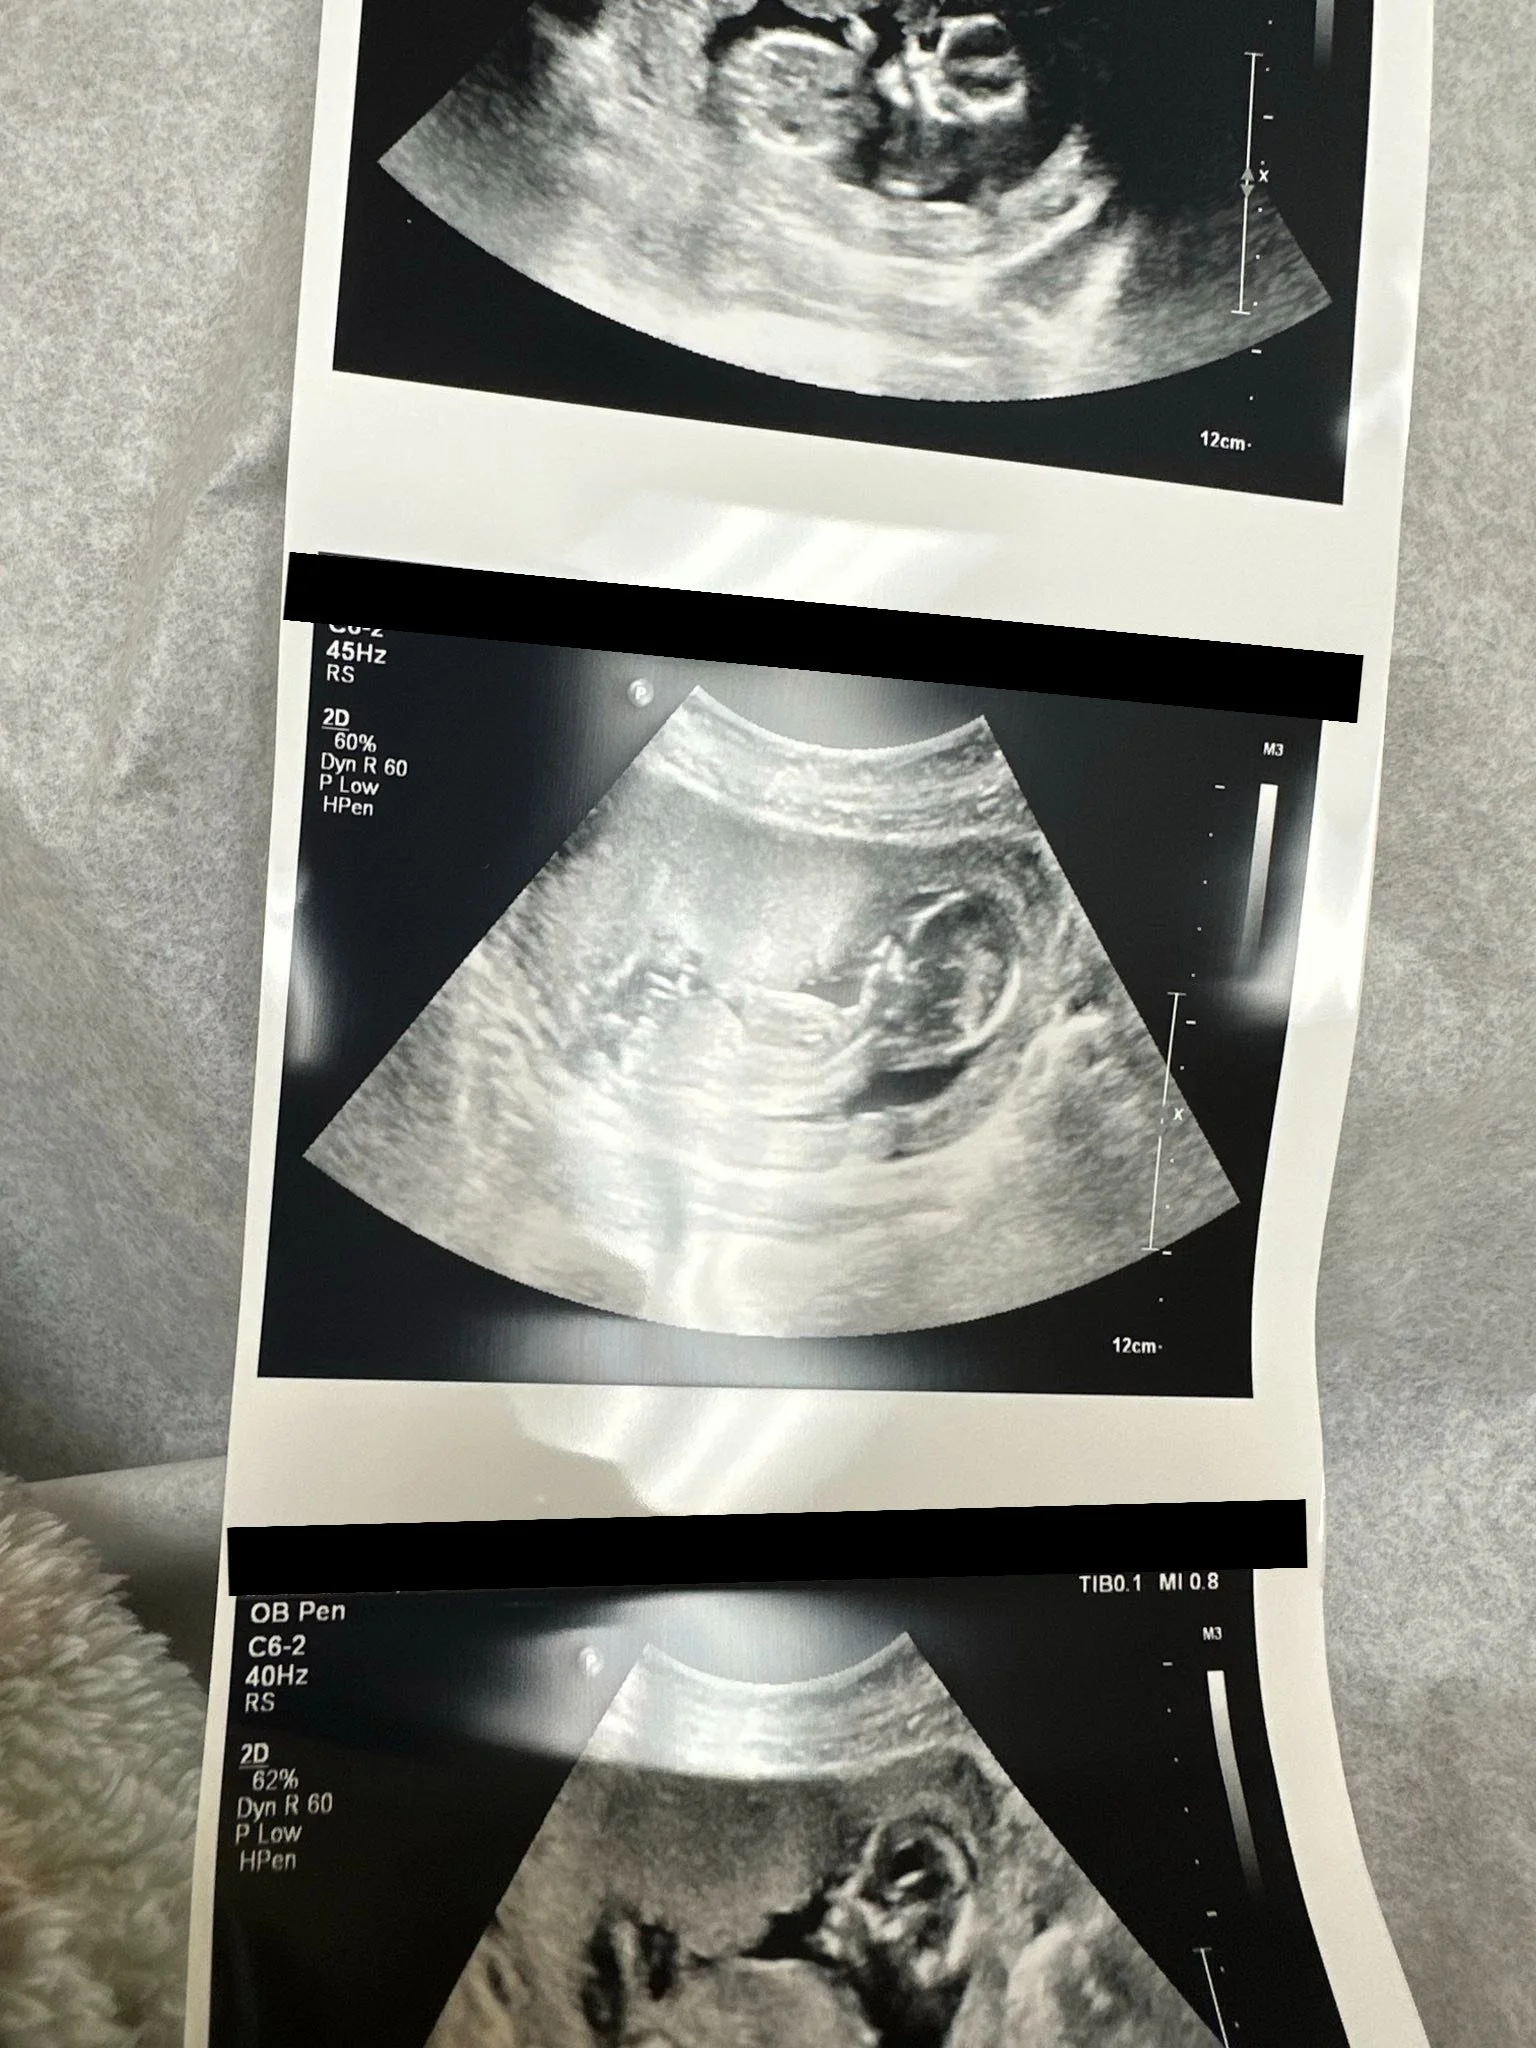

• We were also able to speak with a mother that you could just tell the Lord had already been softening her heart and convicting her- she was so broken! After a lengthy conversation, she decided to let her baby live and even sent the ultrasound she got at her OB appointment!

Ultrasound that Mama Y sent!!!